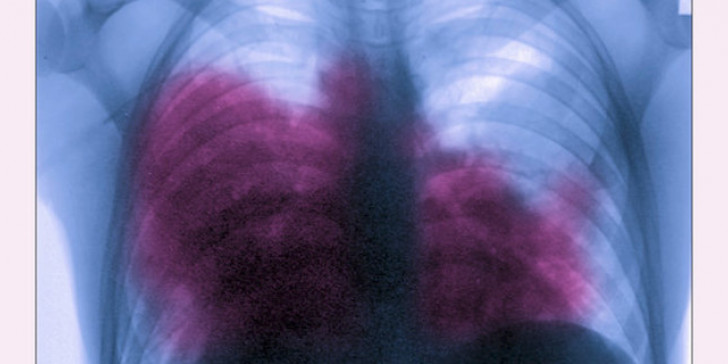

Αν και η νόσος Λεγεωνάριων προσβάλλει κυρίως τους πνεύμονες, μπορεί να προκαλέσει περιστασιακά μολύνσεις σε πληγές και σε άλλα μέρη του σώματος, συμπεριλαμβανομένης της καρδιάς. Μια ήπια μορφή της νόσου Λεγεωνάριων, γνωστή ως πυρετός Pontiac, μπορεί να προκαλέσει συμπτώματα όπως πυρετό, ρίγη, πονοκέφαλο και μυϊκούς πόνους. Ωστόσο, ο πυρετός τύπου Pontiac δεν μολύνει τους πνεύμονες σας και τα συμπτώματα συνήθως εξαφανίζονται μέσα σε δύο έως πέντε ημέρες.